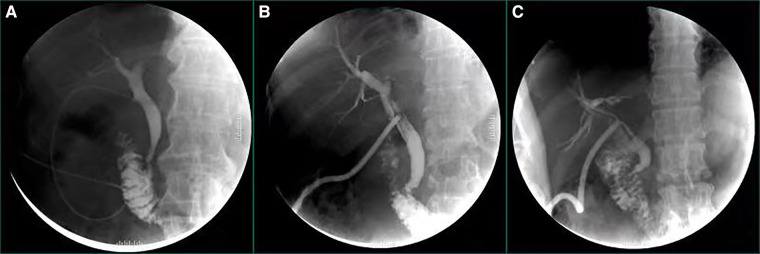

The average time of hospital stay was 11.14 ± 3.63 (days) and postoperative hospital stay was 9.10 ± 3.27 (days) in T-tube group. Compared to T-tube group, the average time of hospital stay and postoperative hospital stay of C-tube group were 9.01 ± 3.49(days) and 7.17 ± 2.10(days), respectively. The patients of C-tube group had shorter in hospital stay, the difference was significant (p < 0.001). The time for placing and fixing T-tube intraoperative was 18.59 ± 2.98 (minutes) and the time of removal T-tube postoperative was 31.05 ± 1.90 (days), the time for placing and fixing C-tube intraoperative was 9.83 ± 2.54 (minutes) and the time of removal C-tube postoperative was 11.77 ± 1.40 (days), The time for placing and fixing C-tube intraoperatively and removal C-tube postoperatively was significantly short (P < 0.001). The distribution of IOC approach was used almost equally in the 2 groups for confirming common bile duct stones and morphological features of bile ducts, there were 57 patients in T-tube group underwent intraoperative angiography, while 77 patients in C-tube group underwent intraoperative angiography, the number in C-tube group appeared to be higer and the difference was significant (P = 0.01). We paid attention to the postoperative biliary drainage situation, therefore, we recorded and statistically analyzed the bilary drainage after the operation. In T-tube group, it was 10.33 ± 3.92 (ml/h) in the first day and 13.27 ± 5.00 (ml/h) in the third day after operation, meanwhile, in C-tube group, it was 9.80 ± 4.50 (ml/h) in the first day and 12.63 ± 5.10 (ml/h) in the third day after operation, There was no significant difference on the rate of bile drainage in the first and third days between 2 groups (day 1 P = 0.287; day 3 P = 0.279). Nevertheless, within 3 days postoperative, there was an increasing trend in bile drainage in both groups. By comparing the rate of bile drainage on the first and third day after operation in both groups, there were significant differences (P < 0.001). (All the data was summarized in Table 2). We can use postoperative cholangiography to further determine the morphological characteristics of the common bile duct, and the presence or absence of residual stones (Figure 2).

This study has also shown that C-tube inserted through the cystic duct had both therapeutic and investigative functions. It not only provided CBD drainage, but also served to inspect the CBD thus avoiding injury and confirming presence of stones. Intraoperative cholangiography through C-tube before choledochotomy could dynamically display the morphological characteristics of bile duct and the contractile function of Oddi’s sphincter, which provided more evidence to confirm the diagnosis of choledocholithiasis, and we called it a “supplementary inspection” for MRCP, CT and B-ultrasound. Usually, there are spiral-shaped folds (Heister valves) at the junction between the cystic duct and the common bile duct, which will be the barrier for C-tube insertion (ref. 22). Inserting C-tube through cystic duct with Laparoscope is a delicate process that requires proficient surgical skills, therefore, we recommend that this type of surgery should be performed by professional hepatobiliary surgeons, meanwhile, surgeons are encouraged to attend the training of LCBDE to reduce the chances that they may seek for help when dealing with difficult CBD stones (ref. 13). Our experiences from this study including (Figure 3): 1. When the surgeon inserts the catheter through cystic duct, it is necessary to adjust the direction of the cystic duct and maintain proper tension to avoid violent manipulation. The depth of the insertion is about 5.0 cm to avoid passing through the odds’ sphincter, C-tube drainage will maintain equivalent to the height of the bile column with normal biliary pressure, external drainage will be “automatic” only when the biliary pressure is higher. Under normal circumstances, the bile enters the intestine along the normal channel through Oddi’s sphincter, which effectively avoids the loss of a large amount of bile. C-tube can be closed and removed at an early stage. 2. The C-tube is always ligated and fixed with a slip knot (Duncan knot) (ref. 23). When tightening the knot, surgeons should not over-tighten it so as to maintain the patency of the drainage tube, however, pipe slippage may be caused by a loose knot. Meanwhile, The Duncan knot can ensure the rapid closure of the cystic duct and avoid bile leakage when the drainage tube is pulled out. 3.After the peak of biliary edema 3 days after operation, patients with C-tube drainage underwent postoperative cholangiography to observe the morphology and function of the biliary tract.